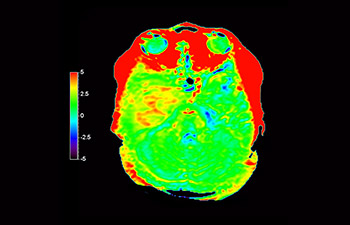

In una società in cui i disturbi neurologici rappresentano un grave problema, Philips si impegna a fornire una efficacia diagnostica senza pari e una guida per il trattamento di tutti i pazienti. Oggi, sebbene la risonanza magnetica sia lo standard di riferimento per l'imaging neuro-oncologico, è comunque possibile migliorarne la precisione nella definizione del grado del tumore e nelle valutazioni di follow-up della terapia. 3D APT (Amide Proton Transfer) è un esclusivo metodo di imaging RM del cervello senza contrasto che permette di ottenere diagnosi più affidabili nel campo della neuro-oncologia. Si avvale della presenza di proteine cellulari endogene per produrre un segnale RM direttamente correlato alla proliferazione delle cellule, un marker dell'attività tumorale. 3D APT è un valido supporto per il personale medico specializzato nella distinzione dei gliomi di grado basso e alto, e nella differenziazione della progressione del tumore rispetto agli effetti della terapia1.

con 3D APT